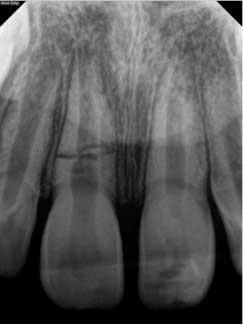

At three months, the clinical testing was equivalent and radiographs showed a fracture still present, but the periodontal ligament (PDL) and lamina dura (LD) were intact and uniform, especially near the fracture line (figure 2). At six months, there was no change in the response to vitality testing and radiographs continued to show no deleterious changes (figure 3).